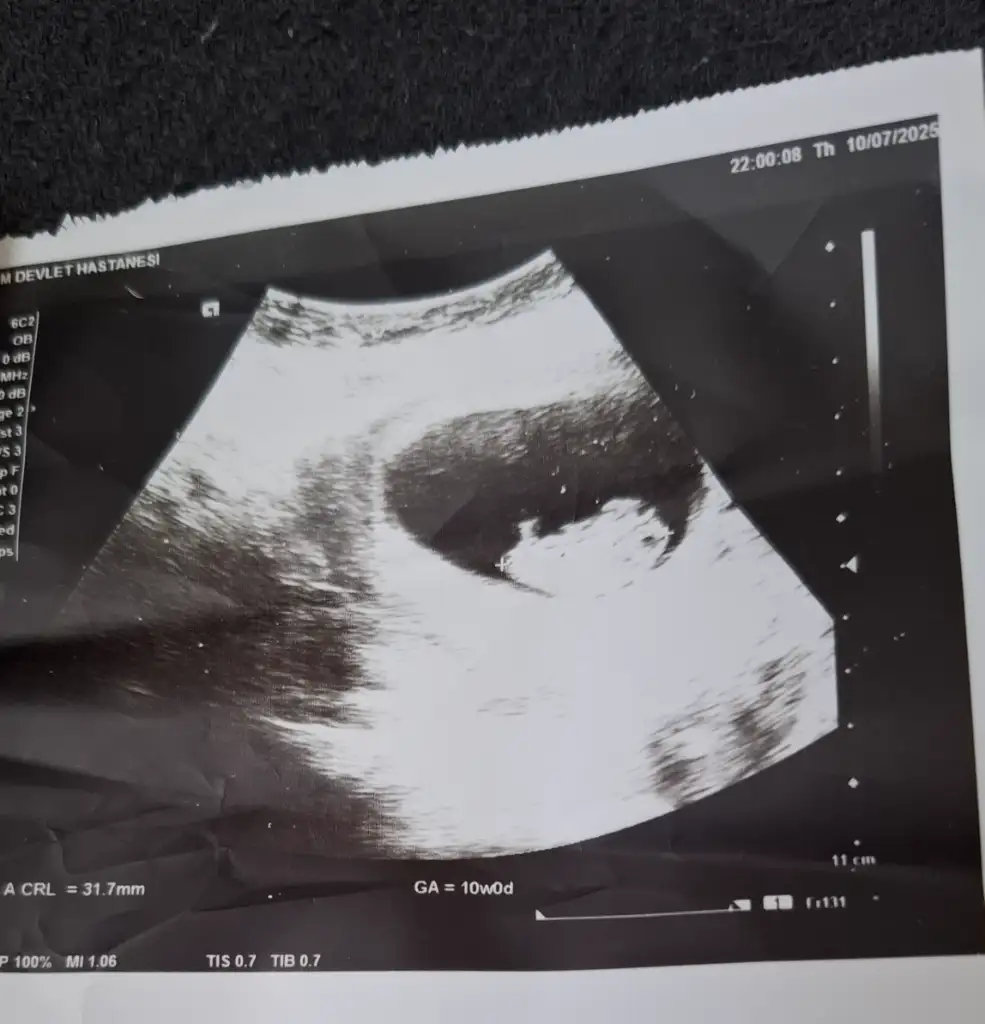

KizzMerhaba ben 10 haftalık hamileyim daha cinsiyeti belli değil ultrason görüntüsünden tahmin edebilecek varmı lütfen çok merak ediyorum.

Kız benceMerhaba ben 10 haftalık hamileyim daha cinsiyeti belli değil ultrason görüntüsünden tahmin edebilecek varmı lütfen çok merak ediyorum.